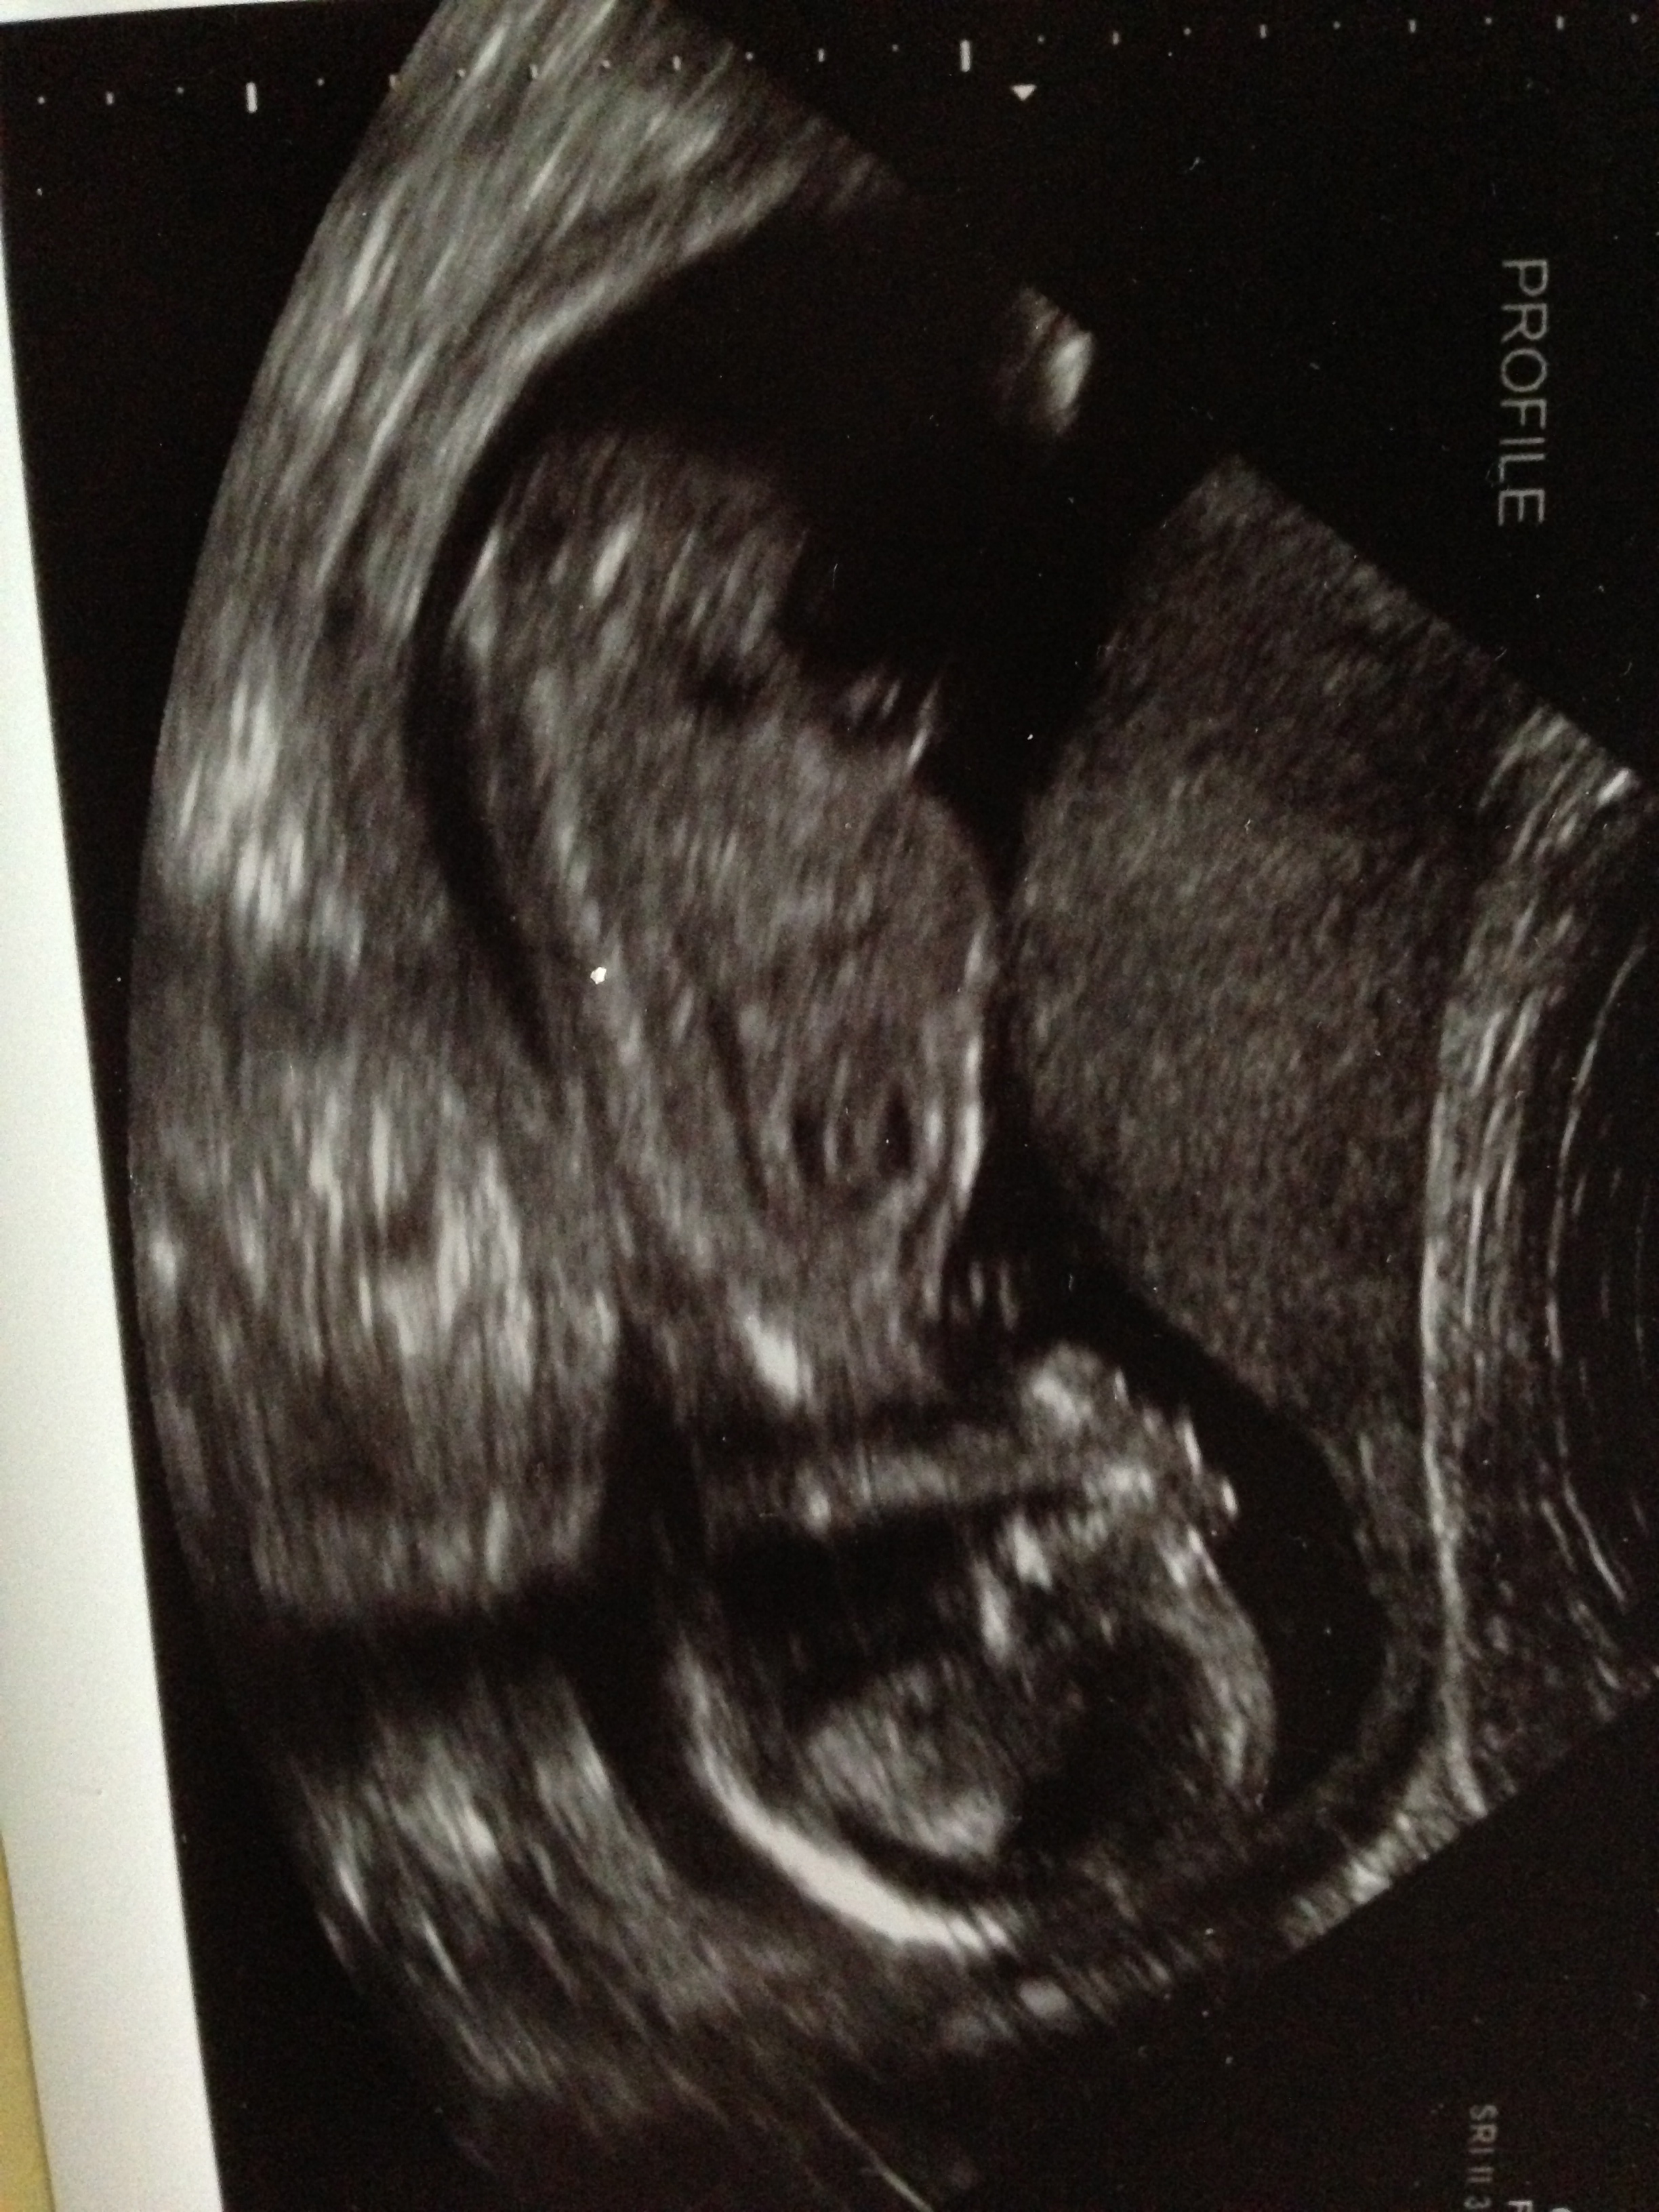

So here it goes. I have the strongest feeling about this child being a girl out of all my others. Seriously never felt this way before. So when I went to my last u/s I was confused. I saw something sticking out that could be a penis, but the part that I didn't understand was that it looked very different from my other boys. Now I am not sure if it is because it was still too early to show a scrotum but we weren't all that close to see much else like lines. When she went digging for the shot it really seemed that she had to come up weirdly from under the bum. I wish I had a potty shot or a side view, but I was in so much shock I forgot to ask.

So with this being said could the tech be wrong? And really how often are they wrong at this stage in the game?